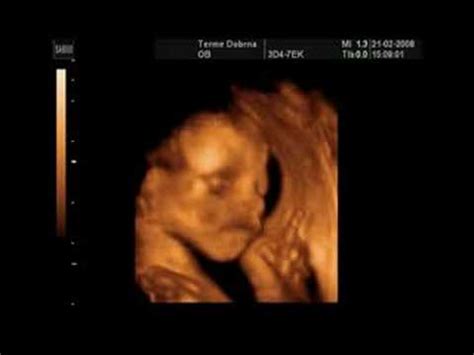

Drugo trimesečje (14. do 26. teden): Plod hitro raste in se razvija. Začnejo rasti lasje, obrvi in trepalnice, telo pa pokrijejo nežni lasje (lanugo). Nosečnica čuti naval energije in povečan apetit, nosečniški trebušček pa postaja vse bolj viden. V tem obdobju se lahko prvič začutijo nežni gibi ploda. Med 20. in 24. tednom se opravi ultrazvočni pregled morfologije ploda, ki oceni njegov razvoj.